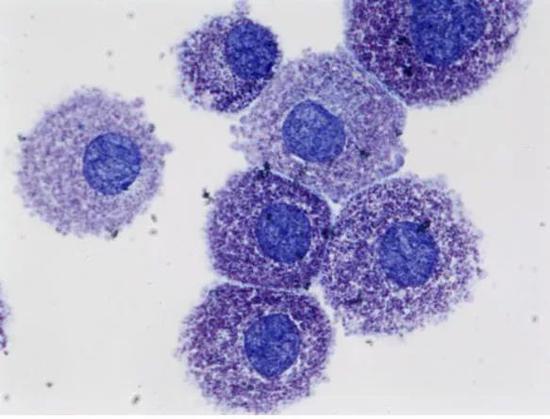

安德鲁·莱恩博士就从病患的基因入手,对小鼠的免疫系统中B细胞开展实验。

他发现唐氏综合征与白血病之间存在某种分子联系。

显微镜下的B细胞

相比正常人来说,患者体内大约有100个基因更为活跃。

而这些基因都在PCR2*的的控制下,影响B细胞的分裂增殖。

以至于B细胞免疫功能可能出现缺陷,从而提高了白血病的患病率。

虽然具体的作用机制仍未探明,但分子层面的规律研究已经是难得的进步。